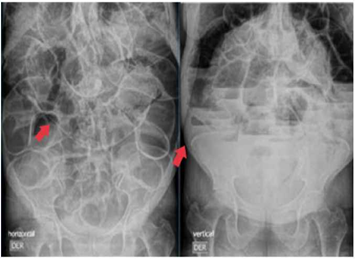

Al ingreso, a la paciente se le realiza, por un lado, radiografía posteroanterior y lateral de tórax con hallazgo incidental de neumatosis intestinal en la flexura esplénica del colon, asociado a la sobredistensión de las asas intestinales y elevación del hemidiafragma derecho e izquierdo, con evidencia de aire subdiafragmático bilateral compatible con neumoperitoneo (Figura 2), y, por el otro, radiografía de abdomen simple, que muestra sobredistensión de asas intestinales, formación de niveles hidroaéreos y ausencia de gas distal (Figura 3).

Radiografía de abdomen simple en decúbito supino y bipedestación. - presencia de aire intraluminal y extraluminal como signo de neumoperitoneo.

Figura 3: Radiografía de abdomen simple en decúbito supino y bipedestación. - presencia de aire intraluminal y extraluminal como signo de neumoperitoneo.

Fuente: Documento obtenido durante la realización del estudio.